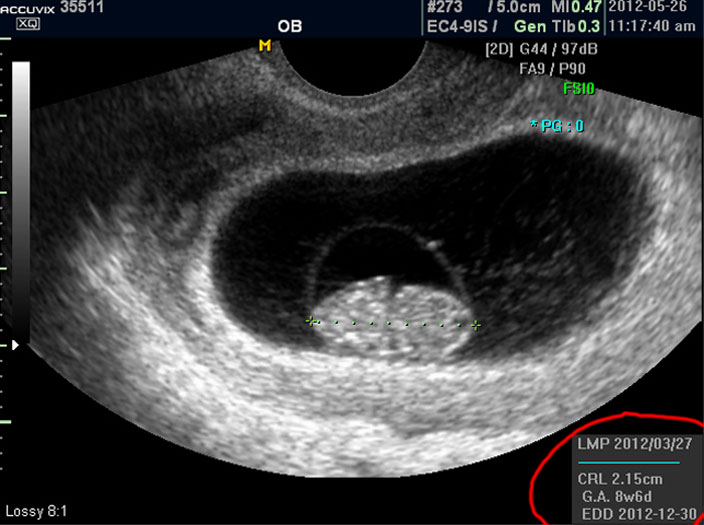

마지막으로 볼 것은 아기의 정보를 나타내 주는 수치들입니다.

으로 우측의 LMP라고 된 숫자는 산모의 최종 월경일이며 이는 초음파로 판단한 것이 아니라 산모의 진술을 바탕으로 한 것인데 이것이 중요한 이유는 초음파는 그저 크기만을 알아 내는 것이라 임신 주수에 걸맞게 잘 자라는지 판단하려면 월경 주기를 알아야 하기 때문입니다.

그 아래 보이는 CRL이라는 것은 Crown Rump Length의 약자로 아기의 머리부터 엉덩이 끝까지의 실제 길이입니다.

임신 12주 내지 13주 정도의 초반기의 아기 발육은 주로 아기의 전체 크기를 가지고 판단하는데 엉덩이까지 체크하는 이유는 흔히 태아는 다리를 구부리고 있기 때문에 성인 인간처럼 머리끝부터 발끝까지 실제 키를 재기가 어렵기 때문입니다.

그 아래 GA 는 Gestational Age의 약자로 우리말로는 태령이라고 하며 초음파의 CRL을 기준으로 했을 때 어느 시기의 태아의 수준인가를 말해 주는 것입니다.

따라서 산모의 LMP를 기준으로 한 태령과 초음파로 측정한 태아의 태령은 1주 정도의 오차로 비슷한 것이 정상이며 간혹 최종 월경일을 틀리게 알고 있거나 아기의 발육에 문제가 있을 때는 큰 차이가 날 수 있습니다.

맨 아래의 EDD는 Estimated Due Date의 약자로 출산 예정일을 말하는데 초음파를 기준으로 했을 때 이정도 시기가 출산 예정일이 될 것이라는 계산입니다.

그러나 이것은 어디까지나 초음파로 예상한 시기이며 실제 출산은 앞뒤로 2주 씩의 오차가 있을 수 있습니다.

상기 이미지는 정지 이미지이기 때문에 심장 움직임과 같은 것은 설명해 드리지 못했지만 이 시기에 중요하게 확인해야 할 점의 하나는 심장 박동의 유무와 횟수입니다.

태아의 심장 박동은 성인보다는 매우 빨라서 보통 분당 120회에서 160 정도 되는 것이 정상입니다.